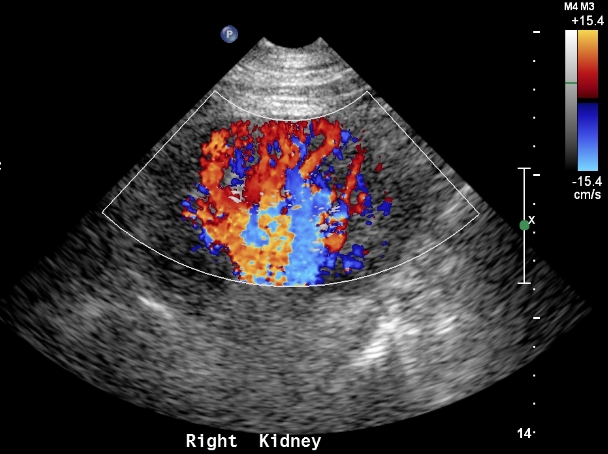

Adding color flow to this view will give a rough estimate of blood flow to the kidney. Before doing so make sure your color scale is set to low flow.

Then, measurements should be taken from the various parts of intra-renal flow. Typically blood flow velocity is sampled in the cortex, medulla and hilum. Cortical and medullary flow should be sampled in the upper and lower poles. A zero angle can be used. These measurements serve to calculate the resistive index.